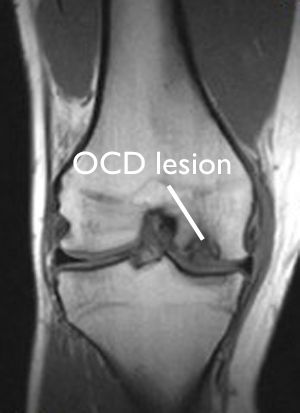

MRI of OCD lesion in knee

This MRI scan shows an OCD lesion in the femur of an 18-year-old patient.